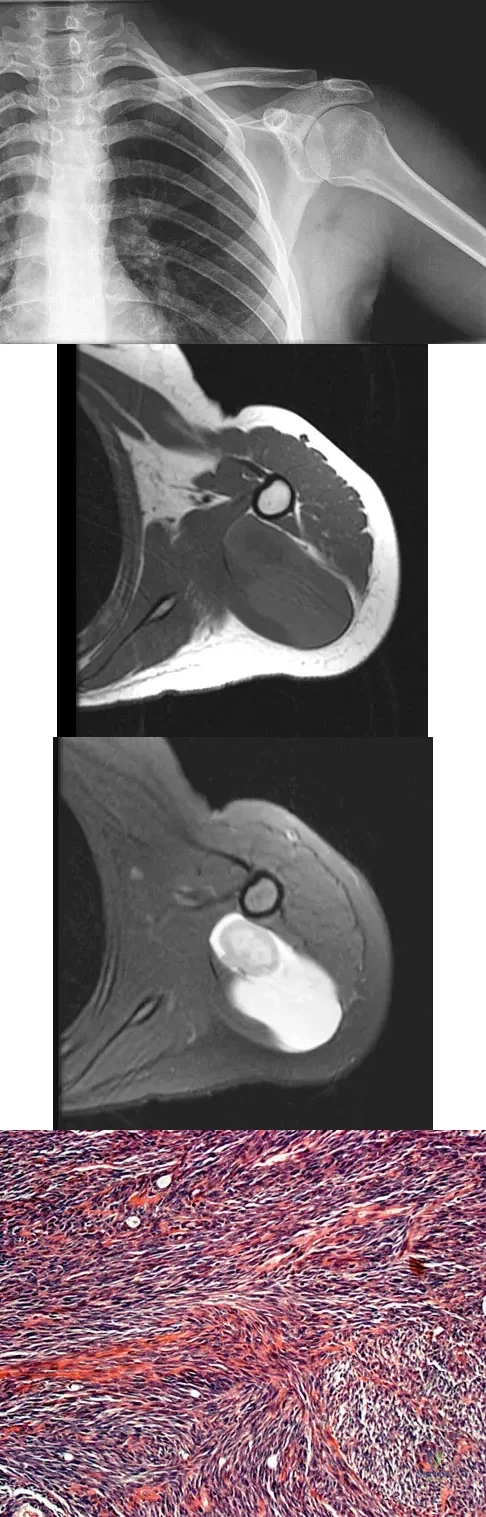

A 16-year-old girl has had painless swelling in her posterior left arm for the past 4 months. A radiograph, MRI scans, and an incisional biopsy specimen are shown in Figures 43a through 43d. What is the cytogenetic translocation most commonly associated with this tumor?

Explanation

A 43-year-old woman is referred after excisional biopsy of a cutaneous soft-tissue mass from her left shoulder. Based on the biopsy specimens shown in Figures 44a and 44b, what is the best course of action?

Explanation